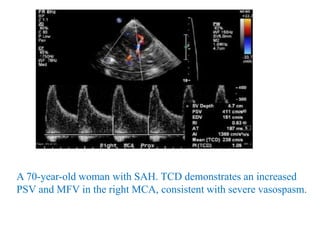

A 70-year-old woman with SAH. TCD demonstrates an increased

PSV and MFV in the right MCA, consistent with severe vasospasm.